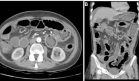

Una tomografía computarizada de control realizada tras el cambio de antibioterapia mostró un preocupante empeoramiento radiológico, con aumento significativo de las opacidades pulmonares que ahora afectaban predominantemente el lóbulo superior derecho y ambos lóbulos inferiores.

La discontinuación del fármaco conduce a una rápida defervescencia y mejoría radiológica en la tomografía computarizada de tórax. Es importante destacar que la neumonía por moxifloxacino carece de hallazgos patognomónicos. Las imágenes por TC consistentemente muestran infiltrados pulmonares, y el diagnóstico se basa principalmente en la asociación temporal entre la exposición al fármaco y la resolución de síntomas.